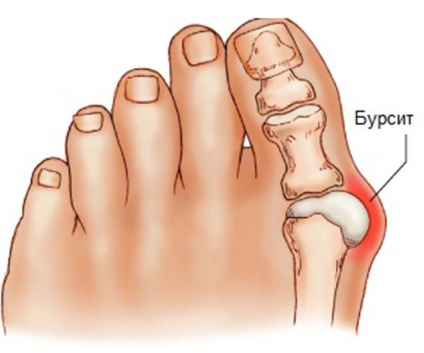

- bursită deget de la picior prima (metatarsofalangian captures comune I);

- Bursită primei articulatii metatarsofalangiene. Adesea declanșat deformare valgus, care crește procesele de frecare și crește presiunea în articulația. Acest lucru duce la țesutul înconjurător constantă trauma, afectează bursa. Manifestat durere în picior, după o lungă plimbare, mai ales în pantofi incomozi cu tocuri. Ca progresia durerii se intensifică, încep să apară chiar și în timpul perioadelor de repaus sau noaptea.

- Bursită primei articulatii metatarsofalangiene. caracteristică externă este deformare vizibilă pe primul picior deget într-o caracteristică „lovituri“, este înconjurat de țesuturi, degetul este rotit în raport cu celelalte degete, există puține umflarea țesuturilor. În perioada inflamatorie acută vizibil roseata externă a pielii, care poate fi fierbinte la atingere.